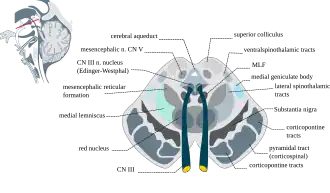

Das Mittelhirn lässt sich grob in drei Schichten gliedern. In der vorne gelegenen Basis des Mittelhirns liegen die Großhirnschenkel (Crura cerebri), nach dorsal folgt die Mittelhirnhaube (Tegmentum mesencephali). Beide zusammen werden auch als Pedunculi cerebri („Großhirnstiele“) bezeichnet. Darauf folgt das Mittelhirndach (Tectum mesencephali oder Lamina tecti). Zwischen Tegmentum und Tectum liegt der beim erwachsenen Menschen etwa 1,5 cm lange Hirnwasserkanal des Mittelhirns (Aquaeductus mesencephali), der vom Zentralen Höhlengrau umgeben wird.[2]

Der Großhirnschenkel zwischen Fossa interpeduncularis (4) und Sulcus lateralis (5) ventral der Substantia nigra (6) führt die corticobulbären und corticospinalen (f, Pyramidenbahn) Fasern sowie daneben medial (g) und lateral (d) corticopontine Fasern langer absteigender Bahnen.

Lange aufsteigende Bahnen sind der Lemniscus medialis (a’, e) und der Lemniscus lateralis (a’), zu den Kerngebieten der Mittelhirnhaube (Tegmentum mesencephali) zählen der Nucleus ruber (7) und Ursprungskerne (8’) des Nervus oculomotorius (8).

Die Haube (Tegmentum) des Mittelhirns ist der große Bereich zwischen dem dorsal liegenden Mittelhirndach (Tectum) und der Abgrenzung beider Großhirnschenkel ventral. Im Tegmentum mesencephali liegen verschiedene Strukturen sowohl von Grauer als auch von Weißer Substanz.

Zu den Großhirnschenkeln beidseits abgrenzend liegt die durch pigmenthaltige Neuronen dunkle Substantia nigra, ein für die Bewegungssteuerung bedeutsames Kerngebiet, verbunden mit subkortikalen Kernen der Motorik von Endhirn und Zwischenhirn (siehe Basalganglien und Parkinson-Krankheit). Sie wird ebenso wie der größte Kern in der Mitte der Haube, der rötliche Nucleus ruber, funktionell dem extrapyramidal-motorischen System zugeordnet. Die Mittelhirnhaube enthält daneben die Ursprungskerne der Hirnnerven III und IV für innere und äußere Augenmuskulatur: Nucleus nervi oculomotorii und Nucleus accessorius nervi oculomotorii (Edinger-Westphal-Kern) sowie Nucleus nervi trochlearis (nahe den unteren Hügeln). Der Nucleus mesencephalicus nervi trigemini ist ein dem V. Hirnnerven zugehöriges Kerngebiet afferenter Neuronen, ähnlich einem Spinalganglion. Weitere Kerne des Tegmentums liegen nahe der Raphe und in der mesenzephalen Formatio reticularis. Das zentrale oder periaquäduktale Grau (Substantia grisea centralis) umgibt den Aquädukt (Aquaeductus mesencephali) genannten Teil des Ventrikelsystems im Mittelhirn. Die Area tegmentalis ventralis ist Teil des mesolimbischen Systems.[3]

Zur Weißen Substanz im Tegmentum gehören insbesondere verschiedene aufsteigende Bahnen, die das Mittelhirn durchziehen. Im sogenannten Trigonum lemnisci liegen Lemniscus medialis, trigeminalis und lateralis beieinander und der Tractus spinothalamicus lateralis nahe unter der Hirnoberfläche. Ventral des Aquädukts verlaufen in Nähe des zentralen Höhlengraus mediales Längsbündel (MLF, Fasciculus longitudinalis medialis), dorsales Längsbündel (Fasciculus longitudinalis dorsalis) und die zentrale Haubenbahn (Tractus tegmentalis centralis). Weitere Bahnen in der Haube gehen von Strukturen des Mittelhirns aus (z. B. Tractus rubrospinalis, Tractus tectospinalis) und kreuzen oder enden hier.